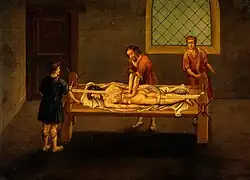

Bei der traumatischen Luxation ist eine umgehende Reposition (Einrenkung) erforderlich, wie sie am Beispiel der Schulter bereits bei Hippokrates von Kos[4] beschrieben wurde. Diese sollte immer schonend und nicht brüsk oder mit großer Kraft erfolgen, da ansonsten die Gefahr von Nerven- und Gefäßschäden sowie Verletzungen des Gelenkes resultieren können. Dass bei der Reposition kein Druck, sondern nur Zug angewendet werden soll, geht auf den englischen Chirurgen und Anatomen Francis Glisson zurück, der 1650 auch die nach ihm benannte „Glissonsche Schwebe“ empfahl.[5] Ist eine Entspannung nicht möglich, erfolgt die Reposition in Analgosedierung oder Narkose. Anschließend muss die Reposition im Röntgen dokumentiert werden, danach erfolgt eine Ruhigstellung (an der Schulter z. B. im Gilchristverband, am Knöchel bei subtalarer Luxation in einem nicht belastbaren Kurz-Gips[6]) und gegebenenfalls weitergehende Untersuchungen zum Ausschluss von Verletzungen der Knochenanteile, der Gelenkkapsel, der Gelenklippe und der umgebenden Bänder.

Luxationen und Luxationsfrakturen wurden seit der Antike mit unterschiedlichen Repositionsmethoden behandelt.[8] In der Antike und später fasste man auch Rückgratverkrümmungen (Verkrümmungen der Wirbelsäule) als Luxationen auf. Dementsprechend erfolgte deren Behandlung durch mechanische Methoden wie der noch von Guido Guidi im 16.[9] und Johann Schultes im 17. Jahrhundert beschriebenen Anwendung des Scamnum (Hippocratis)[10] (griechisch βάθρον), dem „hippokratischen Luxationstisch“. Mit diesem wurden durch Kombination von Druck, Zug und Hebelwirkung (echte) Luxationen wohl häufig erfolgreich eingerenkt.[11]